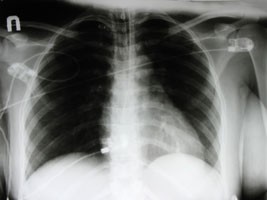

• Képalkotó vizsgálatok: Mellkasröntgen, mellkasi CT